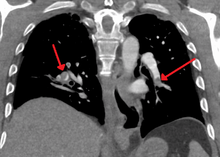

| Chest spiral CT scan with radiocontrast agent showing multiple filling defects both at the bifurcation ("saddle" pulmonary embolism) and in the pulmonary arteries. | |